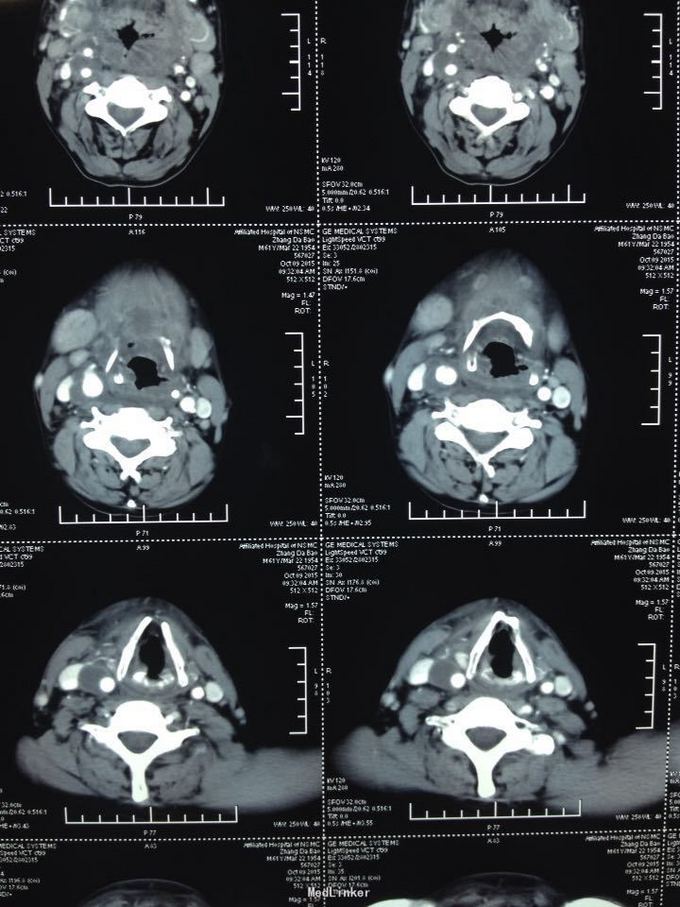

颈部肿痛10多天。10多天前无明显诱因出现颈部及颌下疼痛,肿胀明显,吞咽受限,无伴明显呼吸困难。无高热、寒战等。未特殊处理,上述症状渐加重。

双侧颈部肿胀明显,皮肤稍充血,皮温较高,可触及波动感,压痛明显,右侧为甚,咽部黏膜充血肿胀明显。

颈部多发脓肿。入院后完善相关检查,给予抗感染、对症支持治疗,并于急诊全麻下行颈部脓肿切开引流术,术中分离右侧颈动脉鞘,充分分离脓腔,充分引流。